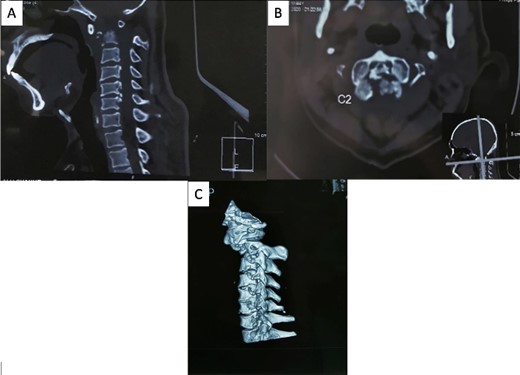

The patient reported sensory disturbances in all four extremities, particularly related to abnormalities in light touch, without any other sensory qualities being affected. A Cervical CT scan revealed a type III odontoid fracture, D’Alonzo type III, with atlantoaxial dislocation, fielding grade 3, and ossification of the posterior longitudinal ligament on the C4-C6 levels (Fig. 1). Cervical MR imaging showed cervical canal stenosis at the C1-C2 level due to atlantoaxial dislocation (Fig. 2). Consequently, we planned to proceed with stabilization surgery. We were unable to perform angiography on this patient due to limited facility resources for such examinations.

A cervical CT scan revealed an odontoid fracture and severe atlantoaxial dislocation. (A) Sagittal view, (B) axial view, and (C) lateral view of three-dimensional CT revealed atlantoaxial dislocation with odontoid fracture.